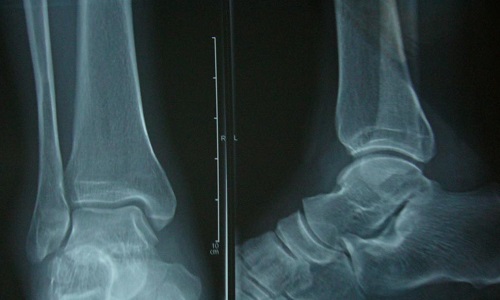

(3)、X线检查:除正、侧位X线摄片外,尚应根据伤情拍摄特殊体位相,如开口位(上颈椎损伤)、动力性侧位(颈椎)、轴位(舟状骨、跟骨等)和切线位(髌骨)等。复杂的骨盆骨折或疑有椎管内骨折者,尚应酌情行体层片或CT检查。

(1)、有外伤史。(2)、上述症状和体征。如肿痛、压痛、畸形等。(3)、X线摄片可见骨折。

伤后踝关节下部肿胀、疼痛、不能站立和负重行走。功能障碍都十分显著,易与单纯踝关节扭伤相鉴别。距骨颈Ⅱ度骨折,踝关节前下部有压痛和足的纵轴冲挤痛。距骨体脱出踝穴者,踝关节内后部肿胀严重,局部有明显突起,踇趾多有屈曲挛缩,足外翻、外展。可在内躁后部触到骨性突起,局部皮色可出现苍白缺血或紫绀。

若为距骨后突骨折,除踝关节后部压痛外,足呈蹠屈状,踝关节背伸蹠屈均可使疼痛加重;若为纵形劈裂骨折,踝关节肿胀严重或有大片瘀血斑,呈内翻状畸形;可在踝关节内侧或外下侧触到移位的骨块突起。

由于跟骨及踝部骨折可与距骨骨折同时发生,有时临床鉴别是困难的,多需X线检查确诊。但距骨后突骨折,对经验较少的医生容易与距骨后大小相似的副骨相混淆,后者是一边缘光滑的子骨,同时距骨后缘也无缺损现象,而距骨后突骨折则相反,应注意鉴别。